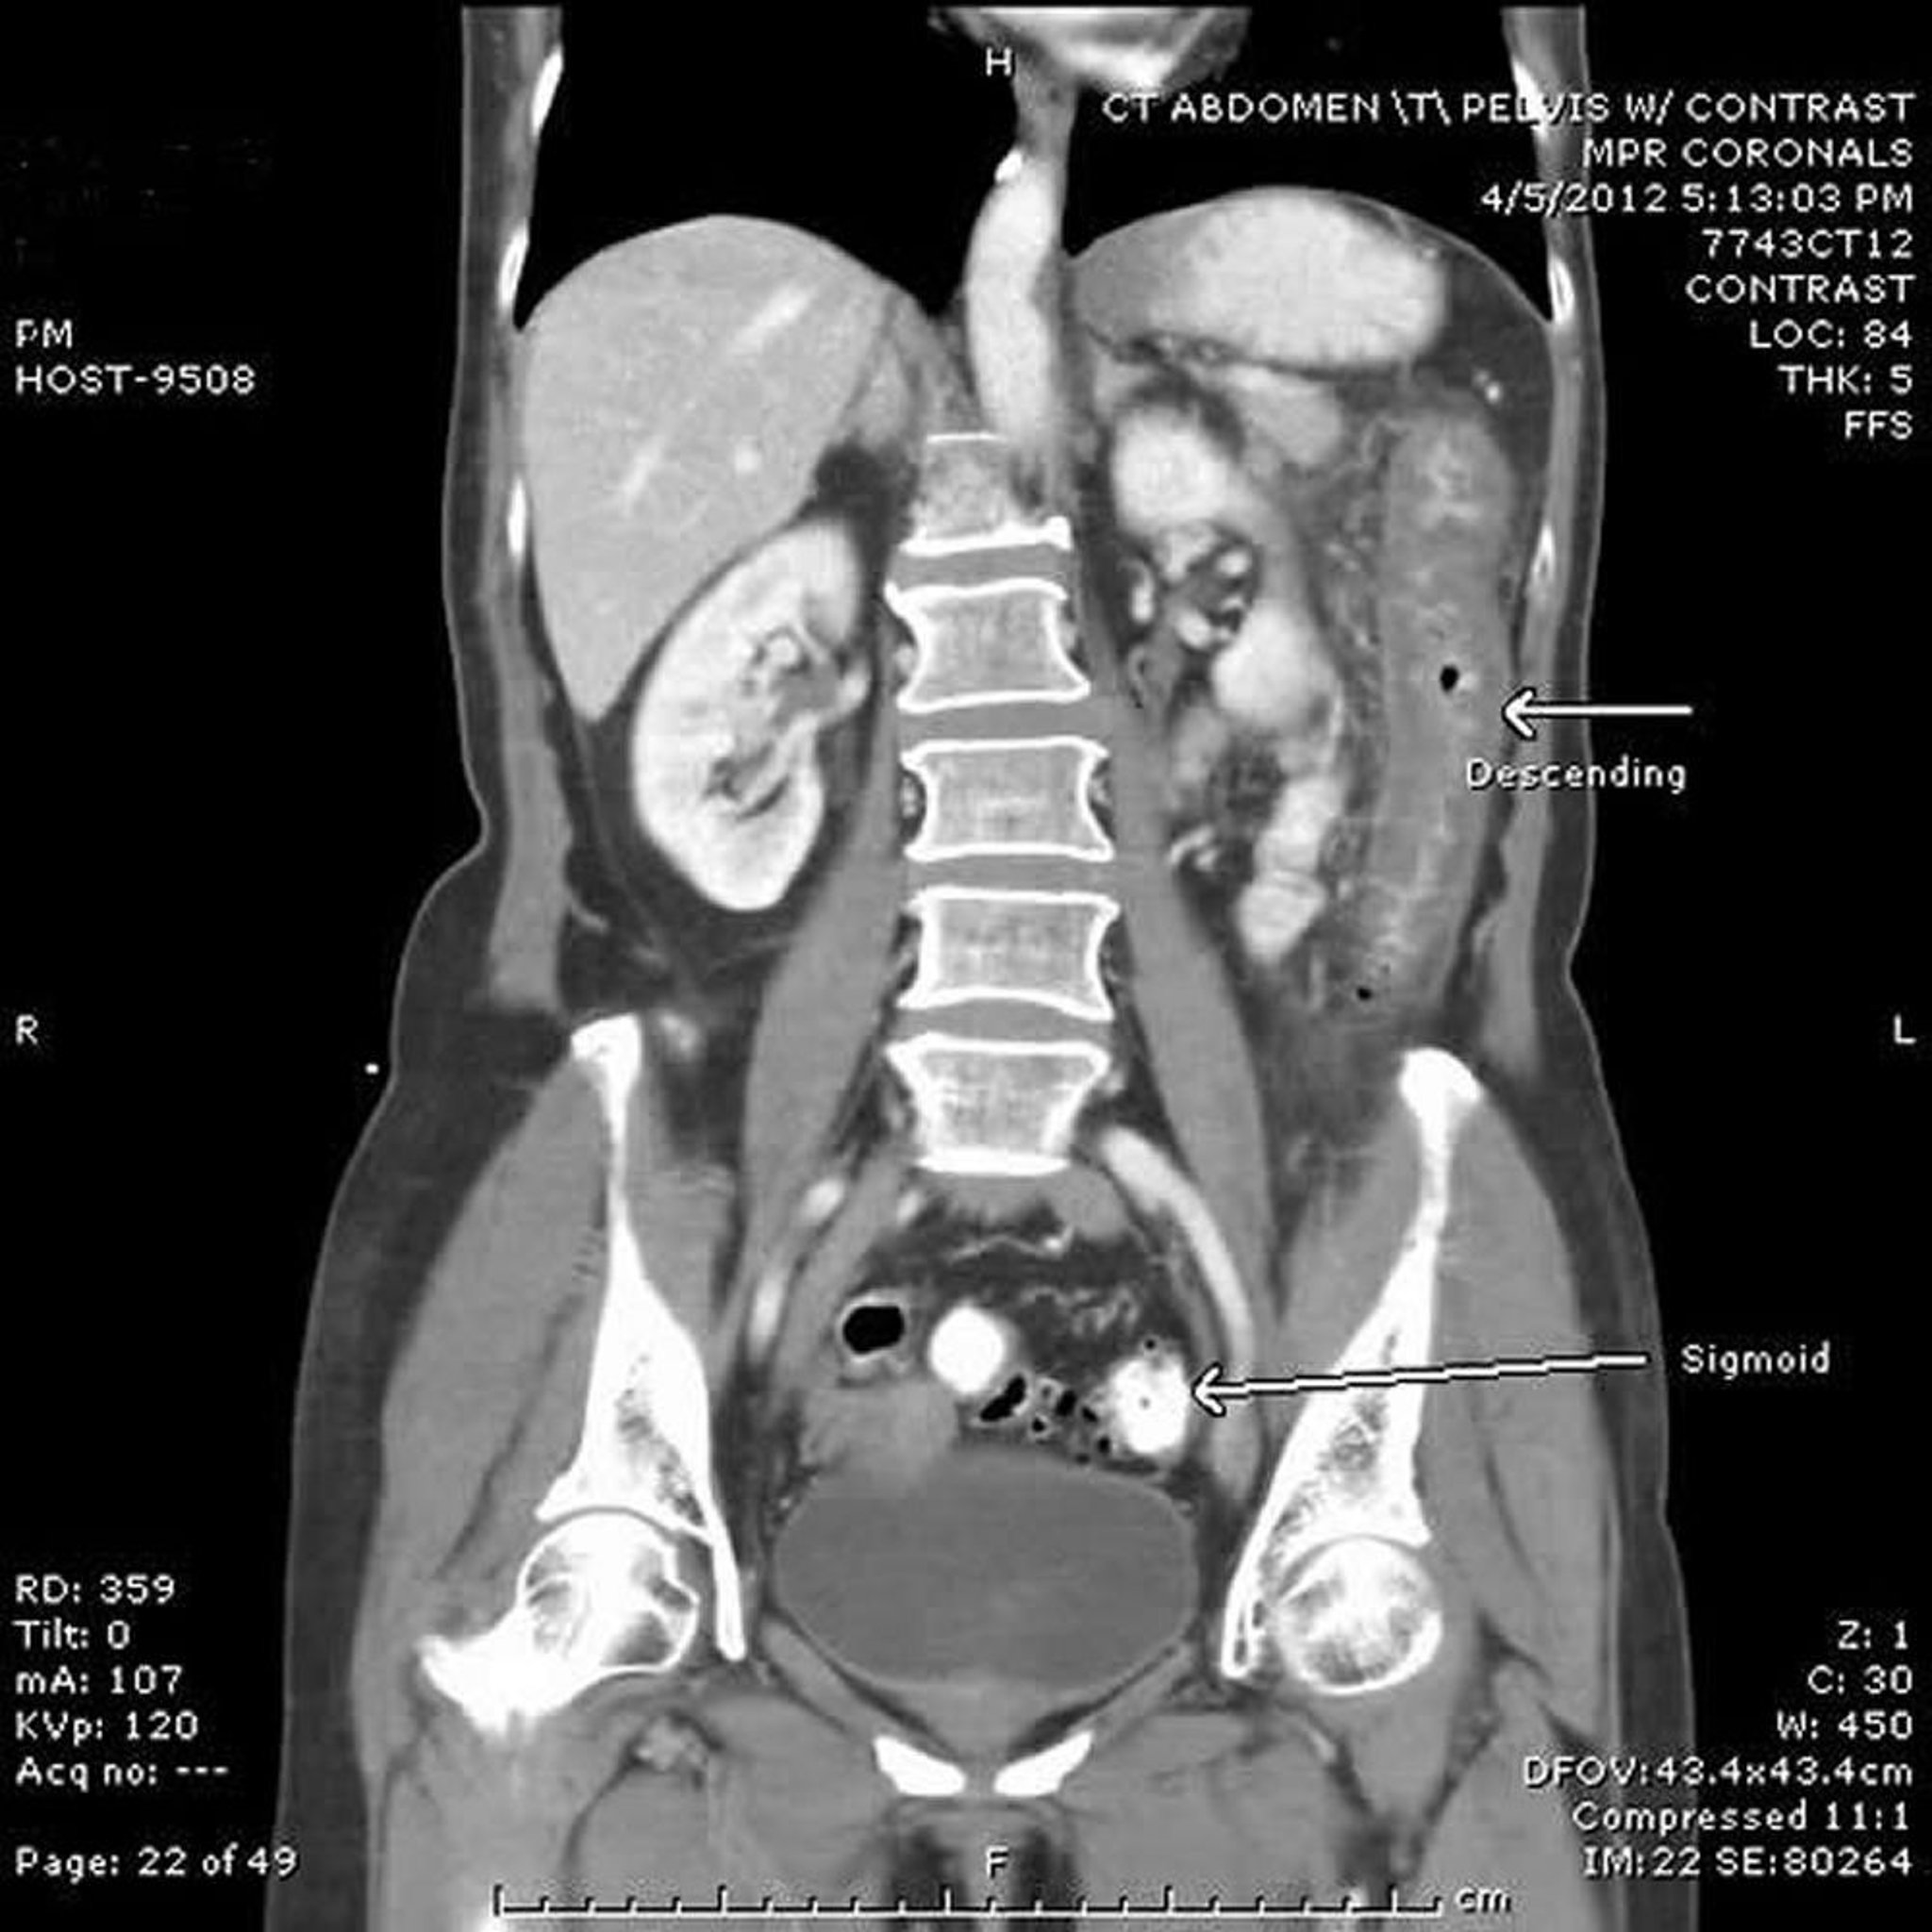

Colite ischémique (TDM)

Dans cette TDM, le côlon descendant (flèche du haut) a une paroi épaisse depuis l'angle colique gauche au côlon sigmoïde proximal. Observer le côlon sigmoïde distal (flèche du bas) avec diverticulose mais sans modification inflammatoire ou ischémique.

Image provided by Parswa Ansari, MD.